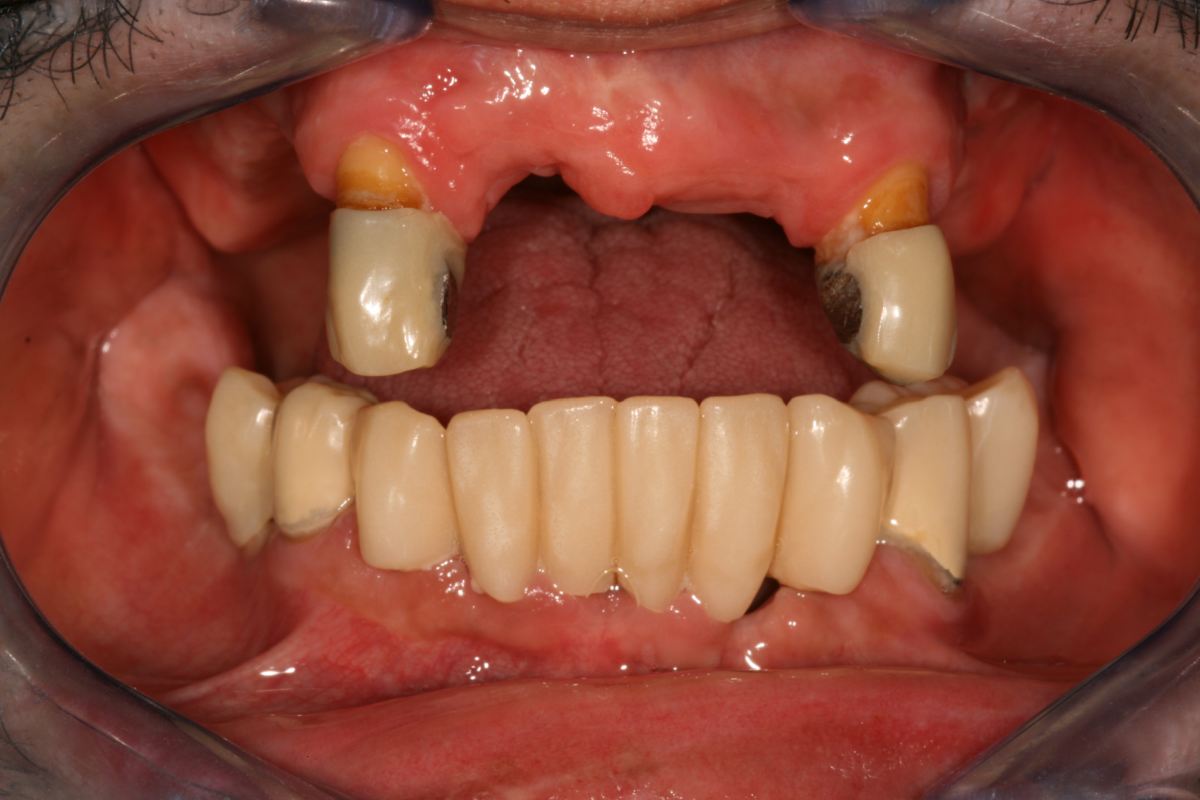

Implantátumok előtte-utána

Fogászati implantátumok előtte-utána

Implantátum beültetés előtt és után

FOGBEÜLTETÉS TELJES FOGATLANSÁG ESETÉN

A legjobb megoldás, amikor 6-8 implantátumot az állcsontba ültetve egy fix híd készülhet a fogsor helyére.

Ideális esetben 8 implantátumra készülhet a 12 fogat pótló híd, mely teljesen rögzített a szájban. A páciens ezt nem tudja eltávolítani.